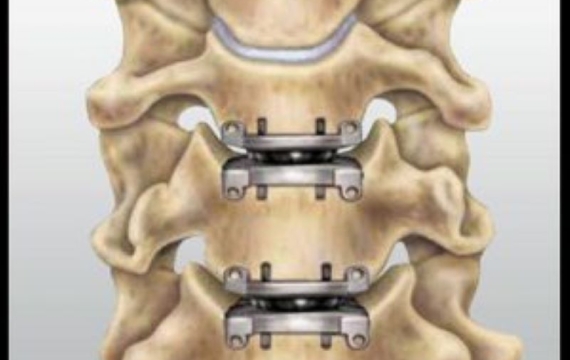

Cirugía de implante de disco cervical artificial

Para aquellos pacientes que sufren de hernias discales en el cuello y quieren evitar la fusión ósea, la cirugía de implante de disco cervical artificial es una opción, ya que esta técnica conserva la movilidad de la columna cervical y no requiere fijación ósea. Con esta técnica, se reemplaza el disco dañado con una prótesis de disco cervical artificial.

Prótesis cervical

Existen varias prótesis de disco cervical en el mercado, que buscan solucionar problemas de fusión y conservar la movilidad de la columna cervical. Las prótesis de disco cervical artificial están hechas con materiales biocompatibles, como el titanio, que reducen el riesgo de rechazo y permiten que los huesos fusionen con el implante.

Resultados y recuperación

La cirugía de implante de disco cervical artificial ofrece buenos resultados a largo plazo y una recuperación más rápida en comparación con la discectomía cervical anterior y fusión. Después de la cirugía, el paciente debe mantenerse en reposo durante unos días, y posteriormente realizar ejercicios de fisioterapia para recuperar la movilidad de la cabeza y el cuello.